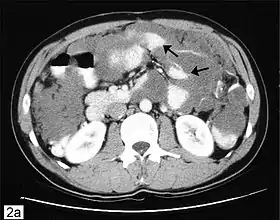

Псевдоміксома очеревини — це накопичення в порожнині очеревини слизових мас з наступним продуктивним запаленням. Слиз потрапляє в порожнину очеревини при розриві цистаденом яєчників чи апендикса. Епітеліальні клітини, що потрапили в порожнину очеревини, імплантуються і ростуть по очеревині, продовжуючи утворювати слиз, що призводить до розвитку хронічного продуктивного перитоніту. Кількість слизових або желеподібних мас іноді досягає декількох літрів. Очеревина виглядає нерівномірно потовщеною, зморщеною. Між органами є численні спайки. У слизистих масах можуть бути виявлені сполучнотканинні клітини та клітини залозистого епітелію. В результаті утворення зрощень можливе формування замкнутих порожнин — кіст різних розмірів, які мають вистилання з циліндричного епітелію, що надає процесу схожість з пухлиною.